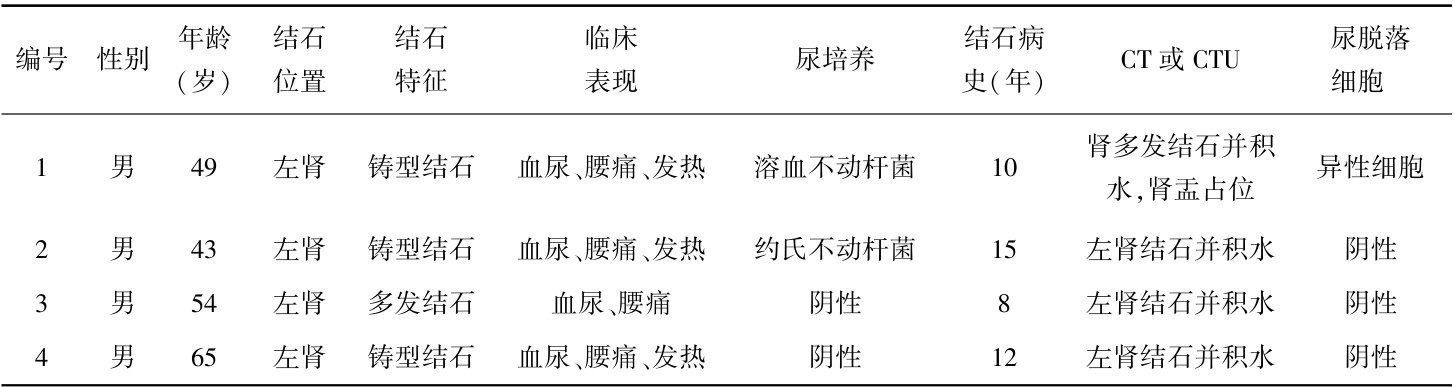

论著·流行病学 | 4例肾结石合并肾盂鳞癌患者的临床诊治分析

论著·流行病学 | 4例肾结石合并肾盂鳞癌患者的临床诊治分析